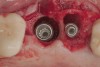

(6.) A 3.6-mm diameter implant was removed with a 4.0-mm diameter trephine drill. The apical portion of the implant was luxated carefully to preserve as much bone as possible.

Figure 6

(7.) Because apical and lateral bone volume was preserved with use of an ultrathin trephine, a wider diameter, 4.2-mm implant was placed at the time of implant removal. Bone augmentation was performed, and submerged healing was selected.

Figure 7

(8.) A cross-linked collagen scaffold consisting of FDBA/DBBM in a 4:1 ratio is placed over the particulate bone graft.

Figure 8

(10.) Primary, submerged closure is achieved over the newly placed implant and regenerative biomaterials.

Figure 10